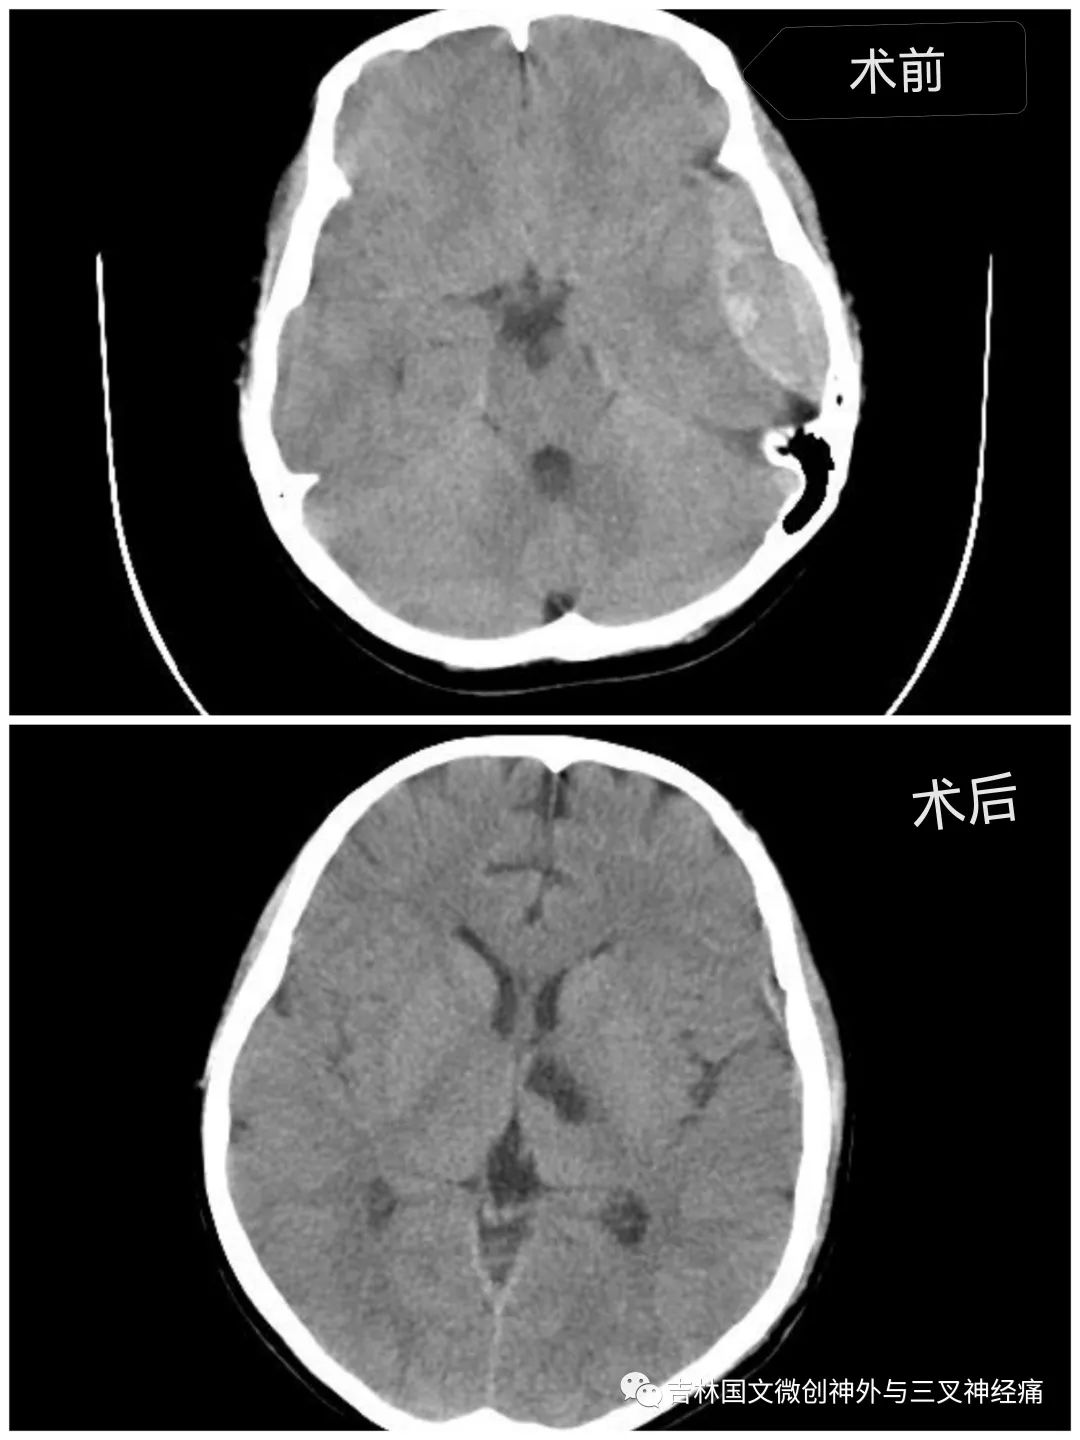

急促的車輪聲刺激著所有人的神經(jīng)?!昂⒆踊杳裕B內(nèi)出血量大,左側(cè)瞳孔散大,已腦疝,需要緊急診開顱手術(shù)”?!跗M主任向家屬交代著。家屬滿臉的焦急,并未有過多的猶豫,立即決定手術(shù)。從病人同意手術(shù)到進(jìn)入手術(shù)室,前后近用了20幾分鐘。

在王芃主任的帶領(lǐng)下,手術(shù)室的鼎力支持下,歷時近4個小時,手術(shù)順利完成。由于病人腦損傷很重,一直處于昏迷狀態(tài)。為了能讓孩子的未來不至于太自卑,少受一點(diǎn)損傷,少留下一道疤痕,王芃主任帶領(lǐng)他的團(tuán)隊用盡一切辦法在努力的保護(hù)病人的氣管(嚴(yán)重腦損傷、長期昏迷的病人,為了能保證呼吸道通暢,增加病人的活命幾率,一般都需要進(jìn)行氣管切開)。